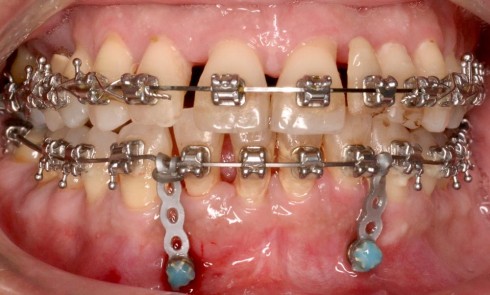

Article réservé à nos abonnés Extraction, implantation et temporisation immédiate : recycler la dent naturelle ? À propos d’un cas clinique

Les protocoles d’extraction-implantation immédiate, décrits pour la première fois en 1976 par Schulte et Heimke [1], se sont progressivement développés...